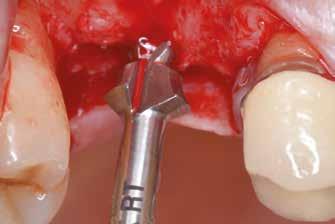

Sebészeti eljárás

Az eljárást helyi érzéstelenítés mellett végeztük (4%-os articaine-hidroklorid 1:100 000 adrenalinnal). Papillakímélő, U alakú palatális bemetszést végeztünk, teljes vastagságú nyálkahártyalebeny preparálás történt, a lebenyt bukkálisan feltekertük (5. ábra). A lebeny bukkálisan feltekert részén de-epitelizációt végeztük el, amellyel kompenzálni tudtuk a bukkális lágyszöveti defektust. Szakaszos előfúrást végeztünk, és a bredent copaSKY 4x10 implantátumot 30 Ncm behajtási nyomatékkal helyeztük be (6. ábra). Az implantátumot 1 mm-re szubkresztálisan helyeztük be, hogy később szélesebb emergenciaprofilt tudjunk kialakítani (7. ábra). Az egyedi ínyformázó úgy készült, hogy kompozitot vittünk fel a titánbázisra, és így formáztuk a lágyszöveteket a transzgingivális gyógyulási fázis során (8. ábra). Az egyéni ínyformázó tulipán formájú, hogy kialakítsa a kívánt emergenciaprofilt. A lágyszövetet feszülésmentesen zártuk #6/0 nem felszívódó, monofil fonallal (Optilene, B. Braun Deutschland; 9. a–b. ábra). Posztoperatív röntgenfelvétel készült, ami alapján az implantátum a szomszédos fogakkal párhuzamos elhelyezést mutatott (10. ábra). Posztoperatív utasításokat adtunk a páciensnek a műtéti terület körüli szájhigiénia fenntartása érdekében. A beavatkozást követő egy héttel a varratokat eltávolítottuk, és a kezelt terület kielégítő gyógyulást mutatott (11. ábra). A 4 hónap utáni késleltetett terhelést a páciens kívánsága szerint terveztük.

1. ábra: Műtét előtti fogászati panorámafelvétel, amelyen a hiányzó felső állcsont jobb első premolárisát és a szabad véggel rendelkező hidat láthatjuk. — 2. ábra: Az implantátum méreteinek megtervezése CBCT-vel. 3. ábra: Bukkális lágyrészdefektus. — 4. ábra: A biológiai szélesség értékelése a vertikális lágyszövetvastagság alapján. 5. ábra: Palatinális „tekercslebeny” – Palatal roll flap. — 6. ábra: Bredent medical copaSKY 4x10 implantátumbeültetés. 7. ábra: Szubkresztális implantátumbeültetés a várható biológiai szélességnek megfelelően.